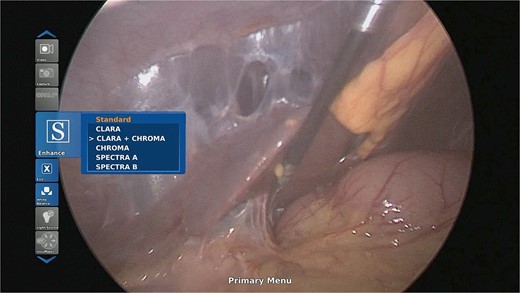

The patient had upper and lower GI endoscopy performed as an outpatient; there was evidence of mild antral gastritis, but no other pathology was identified (Fig. 2). As a result she was diagnosed as having gastroparesis and prescribed prokinetics. She gained no relief of her symptoms with this regimen.

Upper GI endoscopy revealed mild antral gastritis. The duodenum was intubated and had normal mucosa.